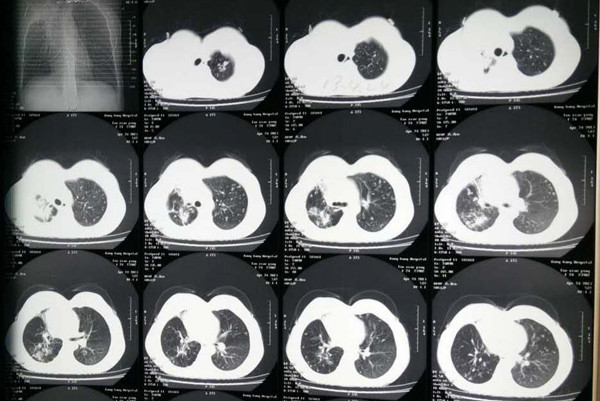

(三)大学新生:肺结核可疑症状问诊和胸部X光片检查。对于一些肺结核高发地区的学生,需要重点开展结核病筛查。